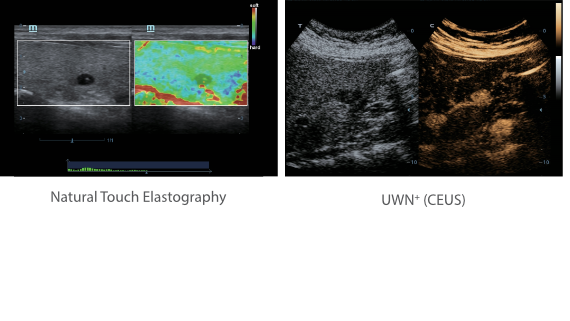

Klinische Bilder